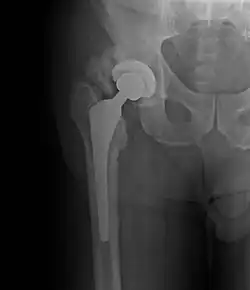

Heterotopic ossification of varying severity can be caused by surgery or trauma to the hips and legs. About every third patient who has total hip arthroplasty (joint replacement) or a severe fracture of the long bones of the lower leg will develop heterotopic ossification, but is uncommonly symptomatic. Between 50% and 90% of patients who developed heterotopic ossification following a previous hip arthroplasty will develop additional heterotopic ossification.